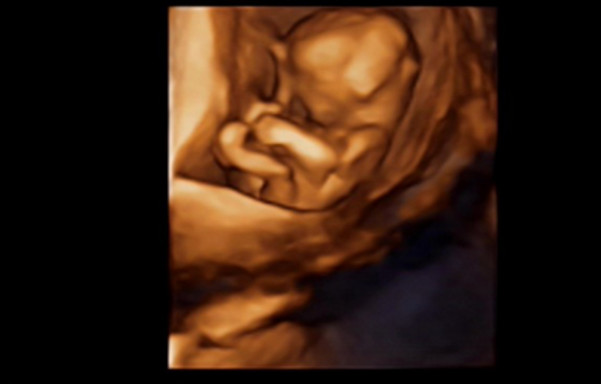

27岁的曹女士,已经怀孕六个月了。三天前,“孕味十足”的她,在丈夫的陪同下来到医院,准备进行提前预约好的四维彩超检查。但是万万没想到,检查结果让她的心情一下跌入低谷!通过影像显示,胎儿嘴唇中间竟然有一指宽的裂痕。经过医生再次仔细确认,腹中的胎儿确实患有唇腭裂,也就是“兔唇儿”。